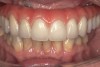

The final restorative solution can be either fixed or removable. Fixed solutions may include: computer-aided designed/computer-aided manufactured (CAD/CAM) fixed prostheses with a titanium (Figure 8 and Figure 9) or zirconia (Figure 10 and Figure 11) framework; fixed prostheses with a CAD/CAM-designed titanium or zirconia framework with acrylic veneering (Figure 12); or fixed prostheses with cast metal and veneering porcelain. Removable solutions may include a milled bar overdenture with attachments, such as locators or an MK1 Attachment (MK1 Dental Attachment GMBH, www.MK1.de) (Figure 13). Removable solutions that allow for simpler hygiene-related practices may be beneficial for elderly patients. In addition, removable solutions may be necessary for patients who require sufficient lip support, as the flange on a removable solution can assist in supporting the contours of the face. It is important to discuss the relative advantages and disadvantages of fixed and removable solutions during the informed consent process.

Fig 9. Intraoral view of the titanium bridge framework with individual lithium-disilicate crowns.

Figure 9

Fig 10. The full-arch zirconia framework with individual lithium-disilicate crowns, which were individually luted

in the laboratory.

Figure 10

Fig 11. Implant-supported full-arch zirconia bridge framework in situ.